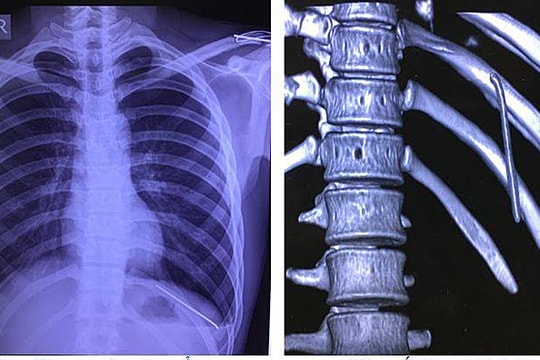

Hospital in Nghe An saves patient with perforated heart due to exploding bullet

August 21, 2020 19:22

(Baonghean.vn) - Nghe An General Hospital has just saved the life of a patient whose heart was punctured by a bullet explosion.